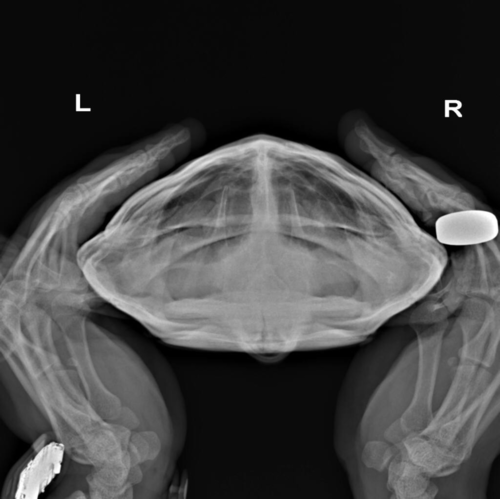

По Воронежу есть информация только о такой клинике, что там могут помочь с черепахой, но на сколько грамотно не могу сказать. В Вашем случае без рентгена в трёх проекциях (или хотя бы в двух) это только гадать пальцем в небо

проекции нужны такие:

обязательно все, что бы там врачи местные не говорили, что это лишнее, что это не нужно и т.п. Это нужно и важно. Только так можно понять состояние лёгких, желудка, репродуктивной системы.

image.thumb.png.3a4129906099ee4692c006bc72e35565.pngimage.thumb.png.ad41f603fd9e257d920b04a60bea2beb.pngimage.thumb.png.2219b5f6e7ddcecb43769ee7fe07e05c.png